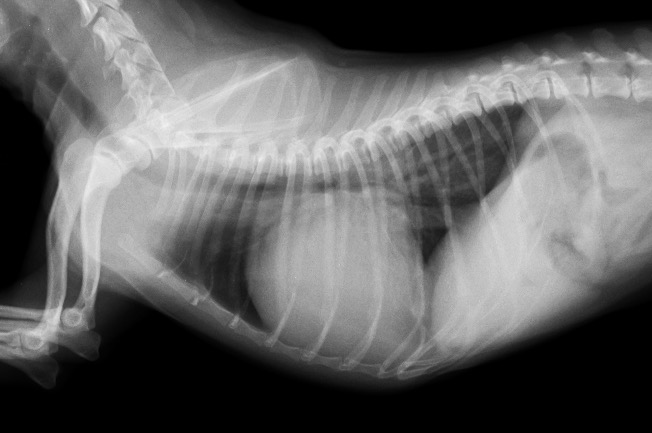

レントゲン検査において、心陰影の拡大(心肥大)が認められ、超音波検査において重度の僧帽弁閉鎖不全症と左心房の拡大が確認されました。

初診時のレントゲン検査 心陰影の拡大